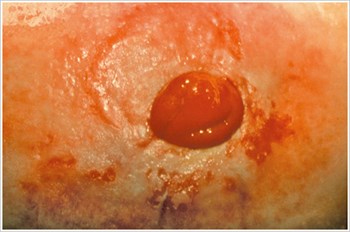

Pressure Ulcer3

Description/Causes:

An ulcer in the peristomal area caused by excessive pressure from an ostomy appliance belt, tight clothing, rigid faceplate, peristomal hernia, or work-related habits.

Symptoms:

- Pain

- Irregularly shaped ulcer

- Pouch leakage

- Decreased wear time